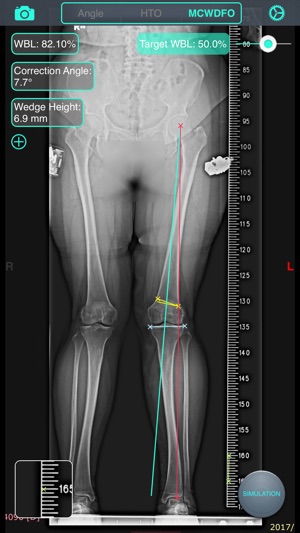

‎截骨神器 - 用于高胫骨截骨术(HTO)和股骨远端截骨术(DFO)的手术前术前规划工具。 特征: 1. 测量骨骼的解剖或力学軸角度,只需通过相机或照片库输入图像。 2. 计算术前负重线(WBL)和规划目标WBL。 3. 自动计算截骨矫正角度、楔块高度、切锯深度与脚长变化。 4. 设定期望WBL,矫正角度,缺口高度,MPTA或LDFA 5. 提供開放(open)或閉合(close)、内侧(medial)或外侧(lateral)截骨。 6. 模拟截骨调整后结果。 教学視頻:https://v.qq.com/x/page/h0527kc4vj1.html 簡体用户指南:http://pan.ba…